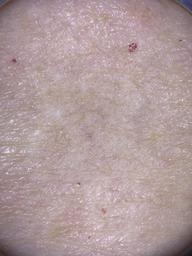

This dataset contains detailed skin tone annotations collected from a prospective, single-center observational study performed at Memorial Sloan Kettering Cancer Center from 2023-2024. The cohort consists of 64 adult patients who underwent full-body skin examinations by board-certified dermatologists. To ensure diverse representation across the spectrum of skin tones, patients were recruited to achieve a balanced distribution across all six Fitzpatrick Skin Types. This dataset was developed to evaluate the reliability of different skin tone labeling methods and to support fairness research in dermatologic AI.

The dataset comprises both patient-level and site-level metadata for skin tone classification using the Fitzpatrick Skin Type scale, Monk Skin Tone scale, Pantone SkinTone Guide, and colorimeter readings (SkinColorCatch, Delfin Technologies). A total of 4,879 dermoscopic images are included. Skin tone assessments were collected across both lesional and non-lesional (normal skin) sites, mapped to standardized anatomic locations. All skin lesions are assumed to be benign, as they were imaged immediately following dermatologic evaluation.